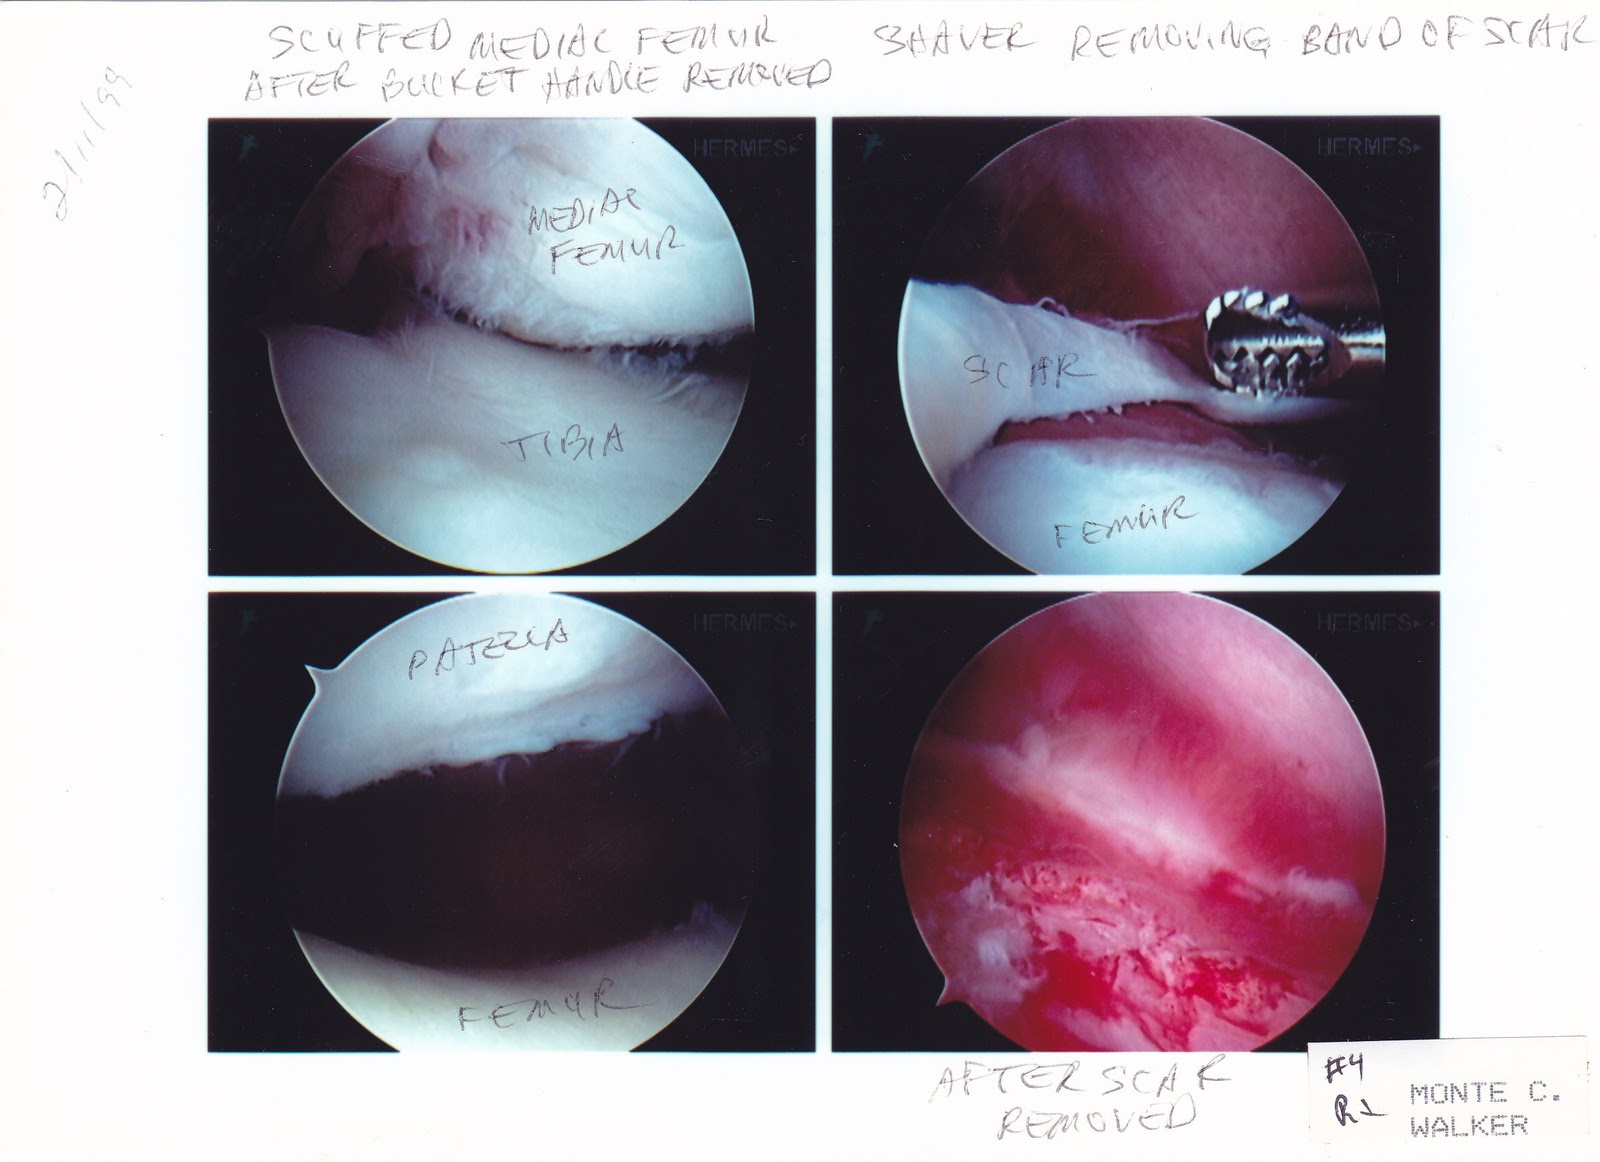

Here are some pics of some of my surg